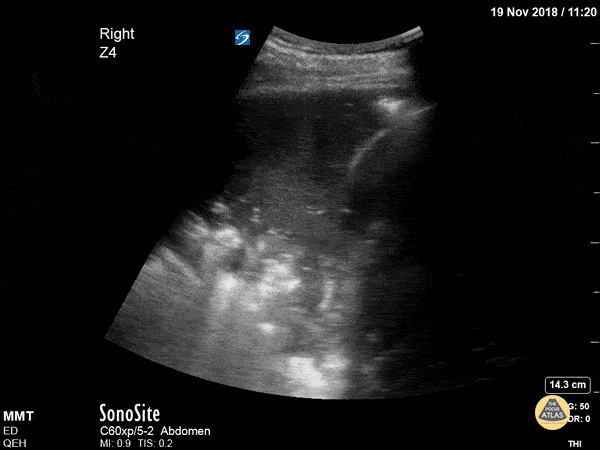

Pulmonary - Dynamic Air Bronchograms in Pneumonia

This patient actually had no cough, no crackles and only subtle changes on CXR but in seconds we had diagnosed pneumonia! Dynamic air bronchograms represent air bubbles moving up and down airways surrounded by alveolar consolidation. Lichtenstein et al compared this finding to static air bronchograms in a 2009 study of 68 ICU patients and found dynamic air bronchograms to be present in 32/52 cases of pneumonia but in only 1/16 cases of atelectasis - a specificity of 94%. Dr. Trauer